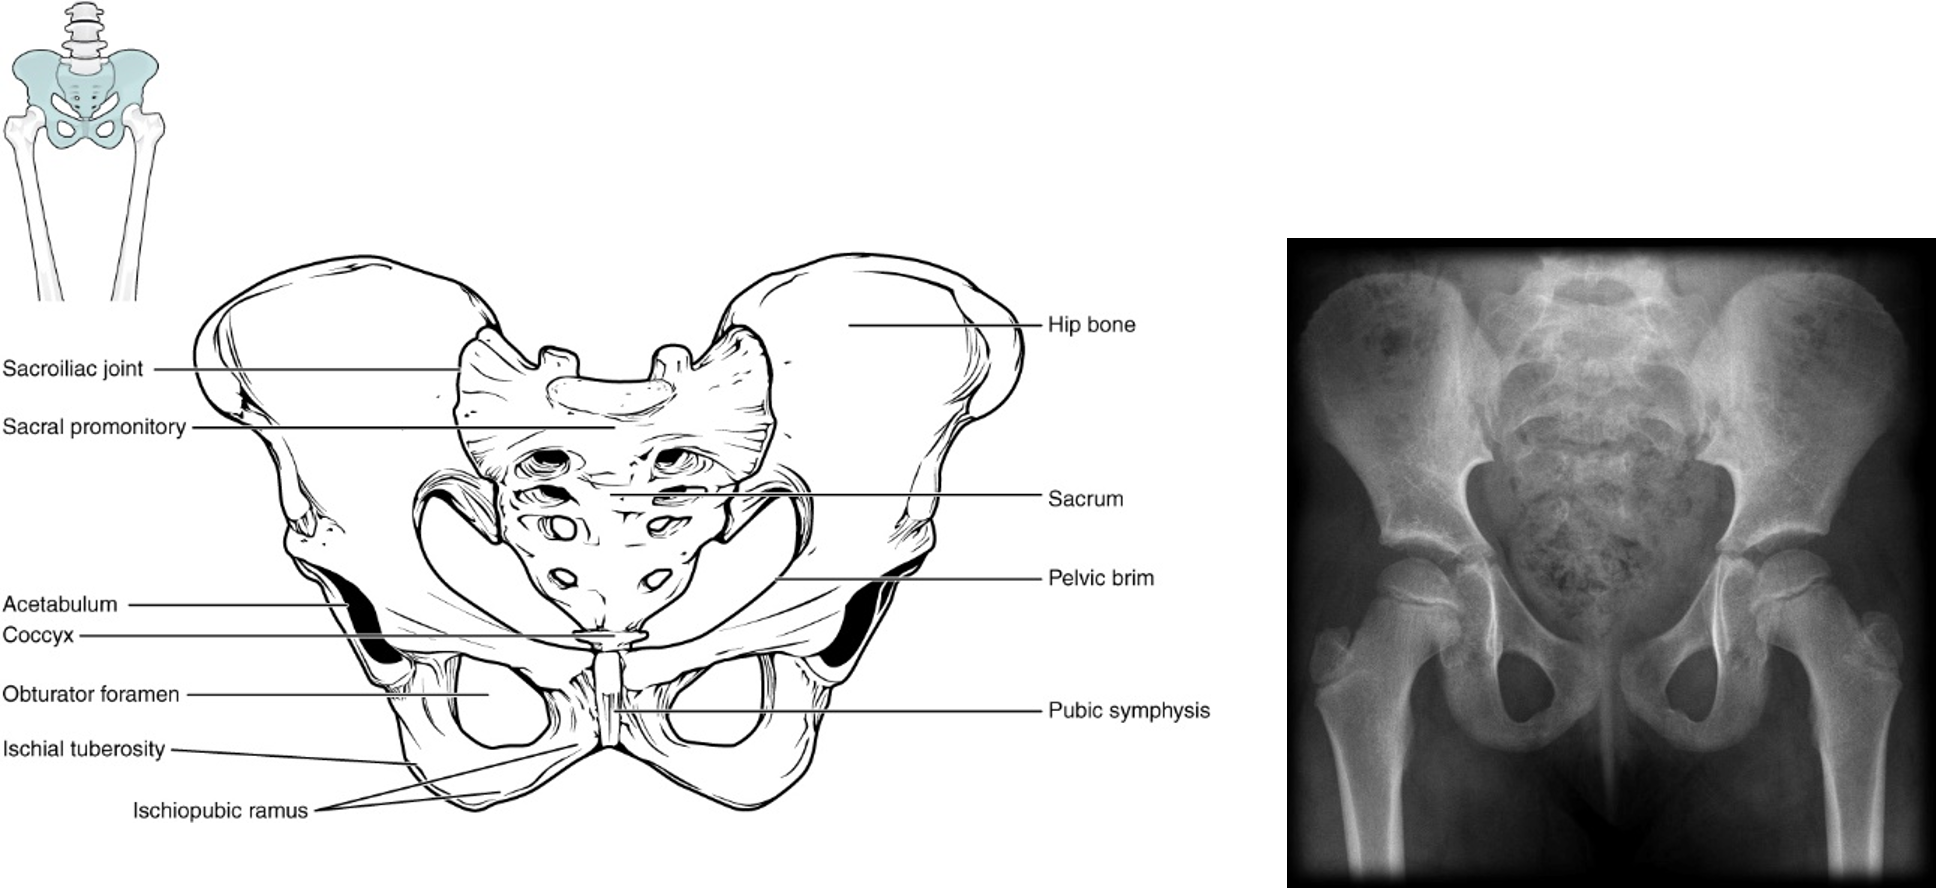

Each pelvic bone (os coxa) is actually 3 bones (ilium, ischium, and pubis) fused together. These bones usually fuse together by 7-9 years of age. In the radiograph of a child’s pelvis (click for source) on the right, you can see the bones are unfused. In the back (posteriorly), each os coxa forms a joint (sacroiliac joint) with the sacrum. In the front (anteriorly), the ossa coxae are united by a piece of fibrocartilage, forming the pubic symphysis. Anatomical features of the female pelvis (below) serve to widen the birth canal to facilitate childbirth.